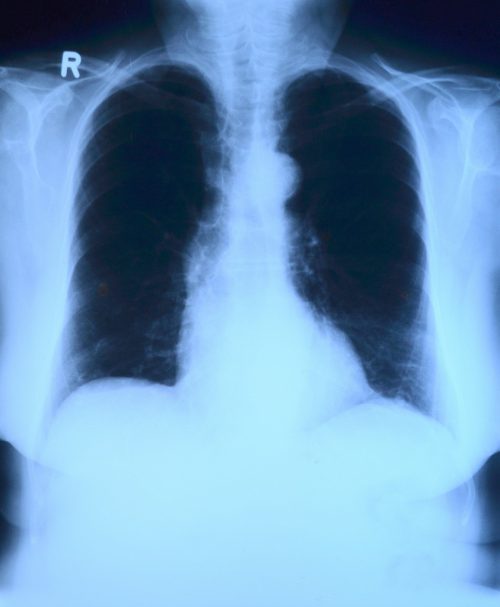

แต่ในทางกลับกัน ลักษณะเฉพาะของผู้ติดเชื้อ Covid-19 ในระยะเริ่มต้น เช่น รูปแบบเฉพาะของจุดขาวที่ปอด การมีไข้ และการตอบสนองของภูมิคุ้มกันในระดับสูง ไม่สามารถที่จะใช้บ่งชี้การเกิดภาวะ ARDS ของผู้ป่วยได้